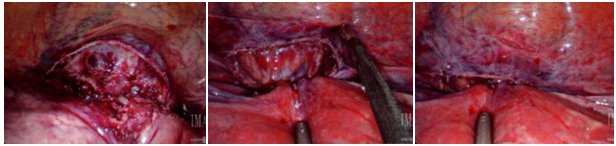

Surgical evaluation revealed an 8-week size, anteverted, mobile uterus with no additional masses; cervix was dilated to fingertip only. A 25mm skin incision was made in the umbilicus and a GelPOINT Mini advanced access single-site laparoscopy device was inserted. Abdominal insufflation revealed vesico-uterine adhesions limiting immediate visualization of the ectopic pregnancy. Due to poor visibility, intraoperative hysteroscopy was performed which revealed a gestational sac at the lower segment of the uterus, adherent to the anterior uterine wall approximately 3-4cm superior to the external cervical os. The RUMI manipulator was placed in the vagina without use of the uterine balloon. The vesico-uterine adhesions were lysed using the Harmonic scalpel and the ectopic pregnancy was exposed within the middle of the scar. Vasopressin was used for hemostasis and the Harmonic was used to incise this area; amniotic fluid with products of conception (POC) was noted and removed (Figure 1). Suction and graspers were used to remove as much POC tissue as possible. The RUMI manipulator was removed, and the endometrial tip was placed to ensure that the os was not closed during the repair. The uterine defect was closed in 3 layers using V-loc sutures (Figure 2). While maintaining observation with the abdominal camera, a suction D&C was performed. The diagnostic hysteroscopy, suction D&C, and SILS robotic resection of the CSEP was performed with an estimated blood loss of 30ml.

Figure 1 Intraoperative images of cesarean scar ectopic pregnancy; products of conception (POC) were noted and removed.